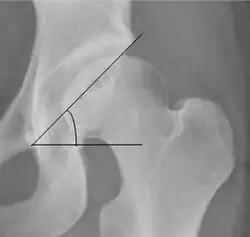

| Tönnis angle |

|

Slope of the sourcil (the sclerotic weight-bearing portion of the acetabulum) | 0 to 10°